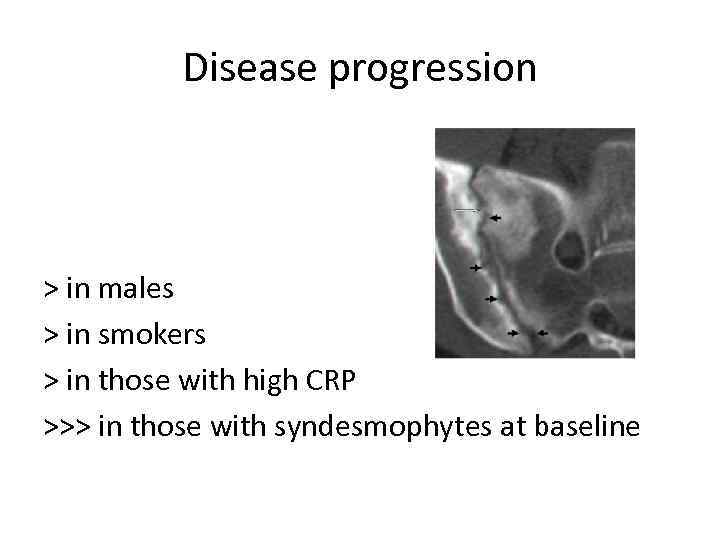

Disease progression > in males > in smokers > in those with high CRP >>> in those with syndesmophytes at baseline